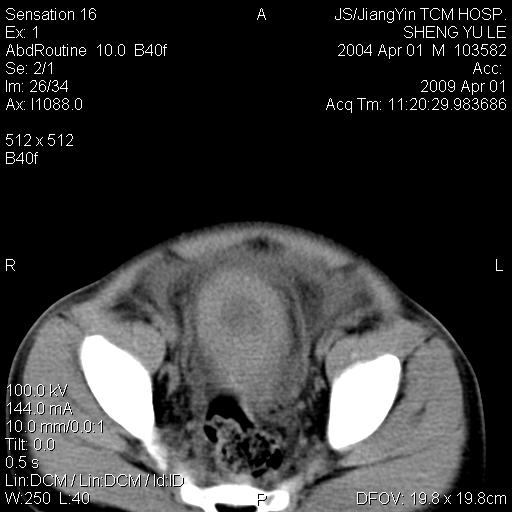

m,5岁。尿痛尿频数天。既往无病史。ct平扫腹盆腔积液。膀胱壁明显增厚。另可见心包增厚。wbc5万,骨髓穿等结果。请指教。

膀胱影像表现结合临床应该是急性膀胱炎症,但为什么有腹水呢?双肾输尿管无扩张,泌尿系压力应该不大不至于引起尿外渗,应该是腹膜感染引起的,但楼主没有提及相关症状,腹膜及膀胱结核?患者白细胞5万(结核不至于这么高啊),脾脏增大,是不是有白血病?进一步检查。。

腹水,膀胱壁增厚,wbc5万,结合临床,支持感染性疾病---感染性腹膜炎、腹水,急性膀胱炎,败血症。期待结果。